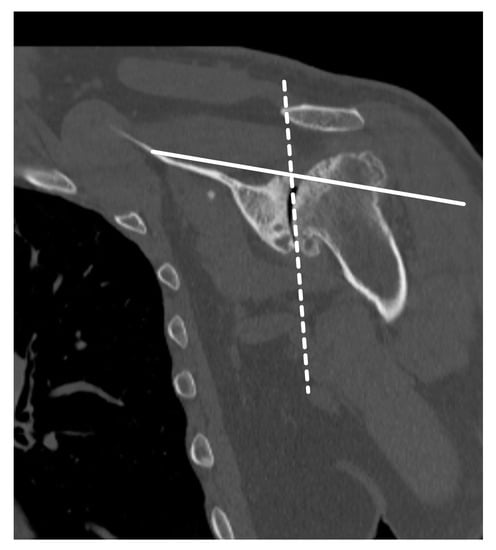

3. Preoperative Imaging

- Sharifi, A.; Siebert, M.J.; Chhabra, A. How to Measure Glenoid Bone Stock and Version and Why It Is Important: A Practical Guide. Radiographics 2020, 40, 1671–1683. [Google Scholar] [CrossRef]

- Budge, M.D.; Lewis, G.S.; Schaefer, E.; Coquia, S.; Flemming, D.J.; Armstrong, A.D. Comparison of standard two-dimensional and three-dimensional corrected glenoid version measurements. J. Shoulder Elb. Surg. 2011, 20, 577–583. [Google Scholar] [CrossRef]